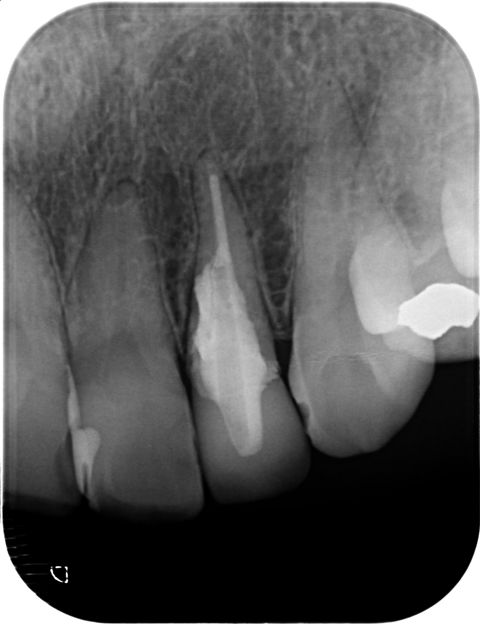

この症例の16ヶ月経過です。

赤い線で囲まれた部分が病変です。原因はパーフォレーション。

歯根破折の心配は消えませんが、病変はほぼ消えてlamina dura(歯槽硬線)も現れてきています。良好な経過を患者さんに伝えることができた時は晴れやかな気持ちになります。